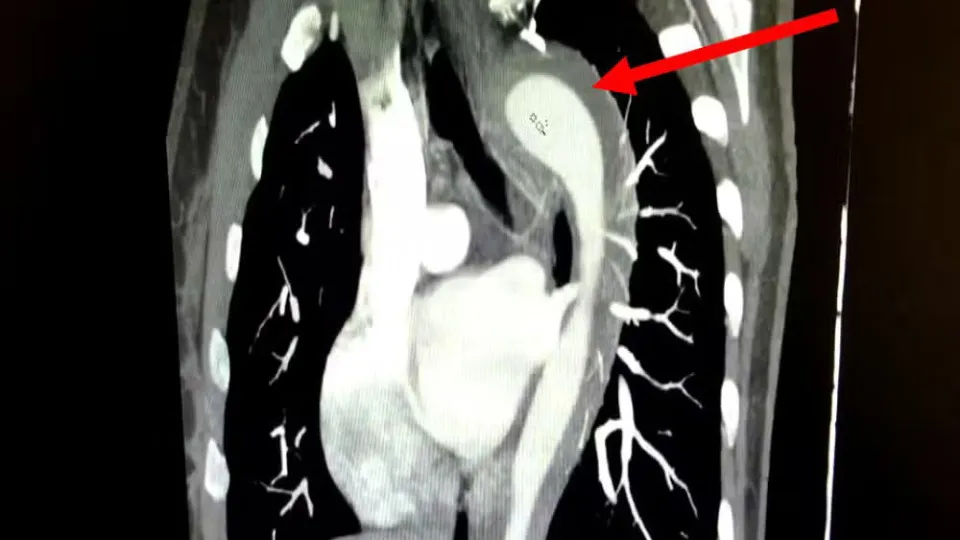

Exames de imagem revelaram um hematoma intramural na aorta, condição grave e pertencente ao grupo de doenças classificadas como Síndrome Aórtica Aguda (SAA). Trata-se de um sangramento interno na parede da principal artéria do corpo, que pode evoluir rapidamente para quadros fatais se não for tratada a tempo. A taxa de mortalidade da SAA aumenta em cerca de 1% por hora quando não há intervenção médica, e até 22% dos casos só são diagnosticados após o óbito do paciente.